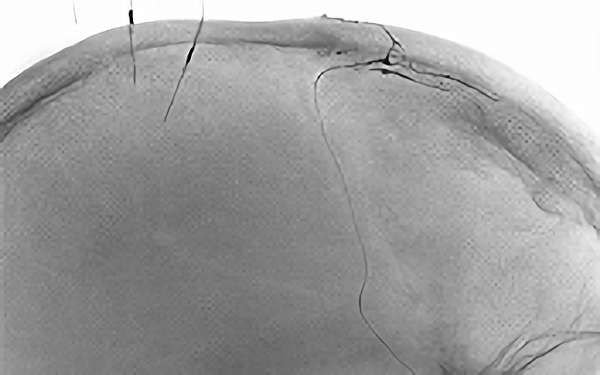

715

'19年12月17日

脳動静脈瘻

80代

院内外来

手術写真

治療

前

中

後

手術日